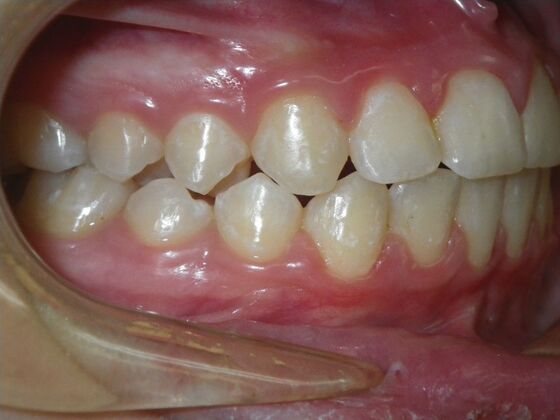

Orthodontics: Case 43

Patient presented with mixed dentition and mild deep overbite, excessive overjet,and rotated lower incisors. She also had a lower bilateral lingual retainer, preventing lower molars from coming forward. She was treated with utility archwires initially, waiting for eruption of cuspids and bicuspids. This was followed by conventional straight wire appliances and upper and lower standard hawley retainers.